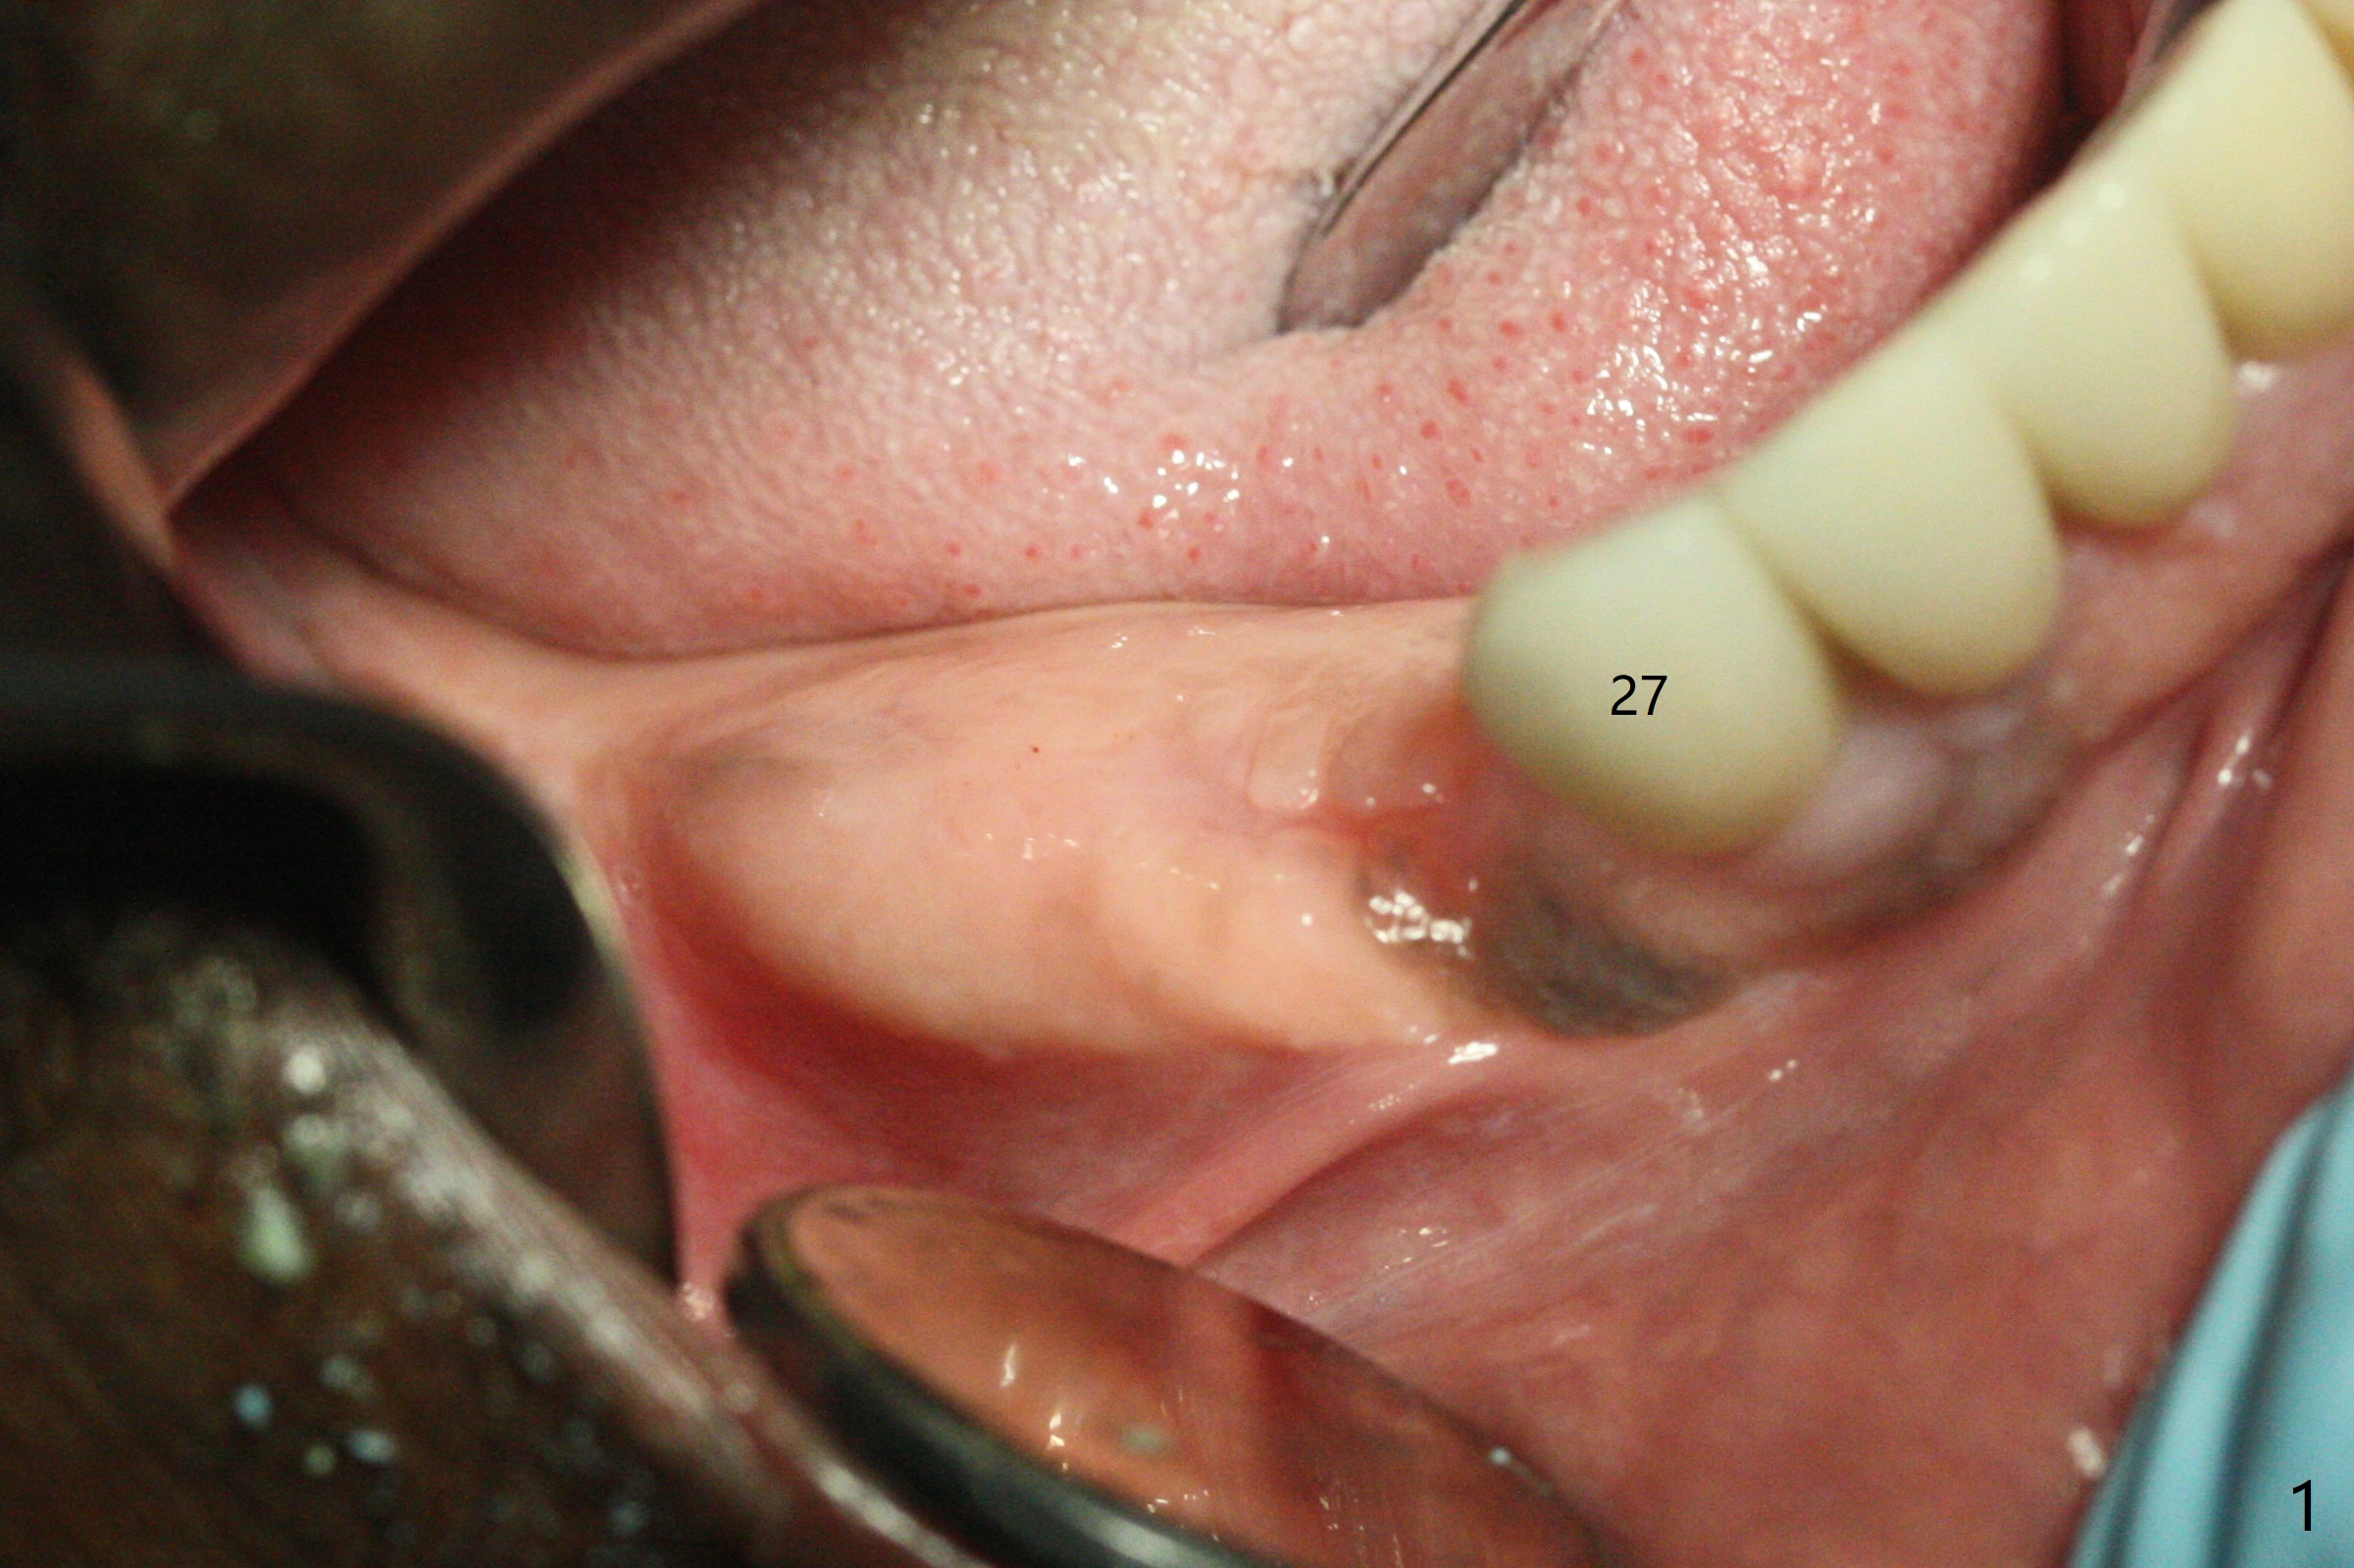

The ridge post bone graft (#28) and socket preservation (#30) is wide. Using a surgical guide (Fig.2), tissue punch is used to initiate osteotomy without compromising the keratinized gingiva (Fig.3). With no stop fixture mount for a 4.5x11.5 mm implant being placed at #28, the osteotomy at #30 is much easier. A 5x17 mm Tatum tapered tap is inserted with the guide and then without the guide. Finally the 5x14 mm tissue level implant is placed free hand (Fig.4). With underdrilling at #30 (4x10 and 4x11.5 instead of 4.5x10 and 4.5x11.5), primary stability is high. So is #28. Abutments are placed for periodontal dressing (Fig.5).